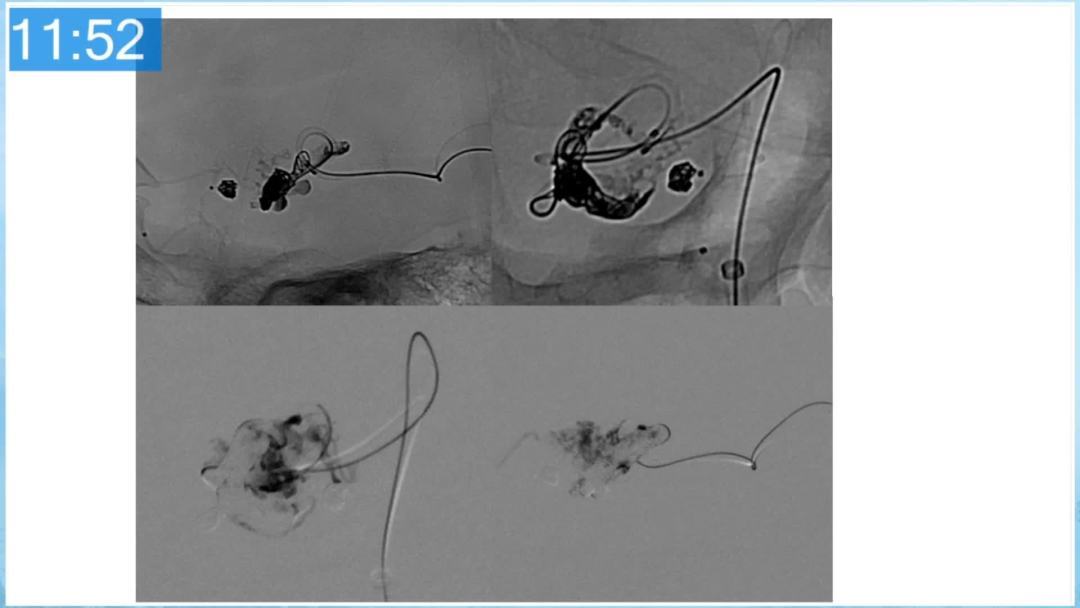

合理的复合平台下的综合治疗,针对每一个病变对应不同方法安全性分析,不预设、不排斥,每种技术发挥到最佳,互相保障。

本期为大家特别分享:空军军医大学唐都医院邓剑平教授的精彩会议内容《颅内动静脉畸形的复合手术治疗》,欢迎大家阅读和分享!